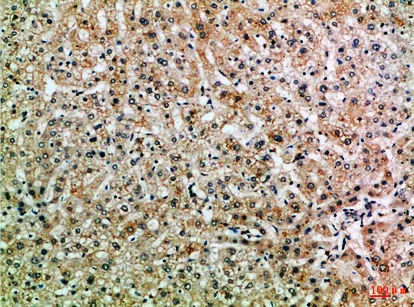

CCL14 Rabbit Polyclonal Antibody($99/20μL)

Cat: APRab08133

Size1:20μL Price1:$99

Size2:50μL Price1:$118

Size3:100μL Price2:$220

Size4:200μL Price3:$380

Application:IHC-P,IF-P,IF-F,ICC/IF,ELISA

Reactivity:Human,Rat,Mouse

Conjugate:Unconjugated

Optional conjugates: Biotin, FITC (free of charge). See other 26 conjugates.

Gene Name:CCL14 NCC2 SCYA14